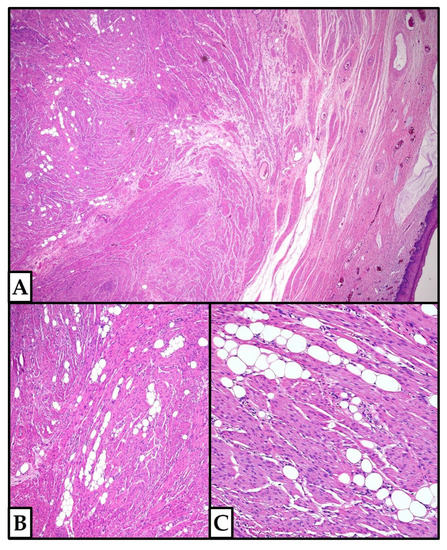

3.1. Our Case Series

3.1.1. Case 1

3.1.2. Case 2

3.1.3. Case 3

3.1.4. Case 4

3.1.5. Case 5

3.2.6. Histopathological Features